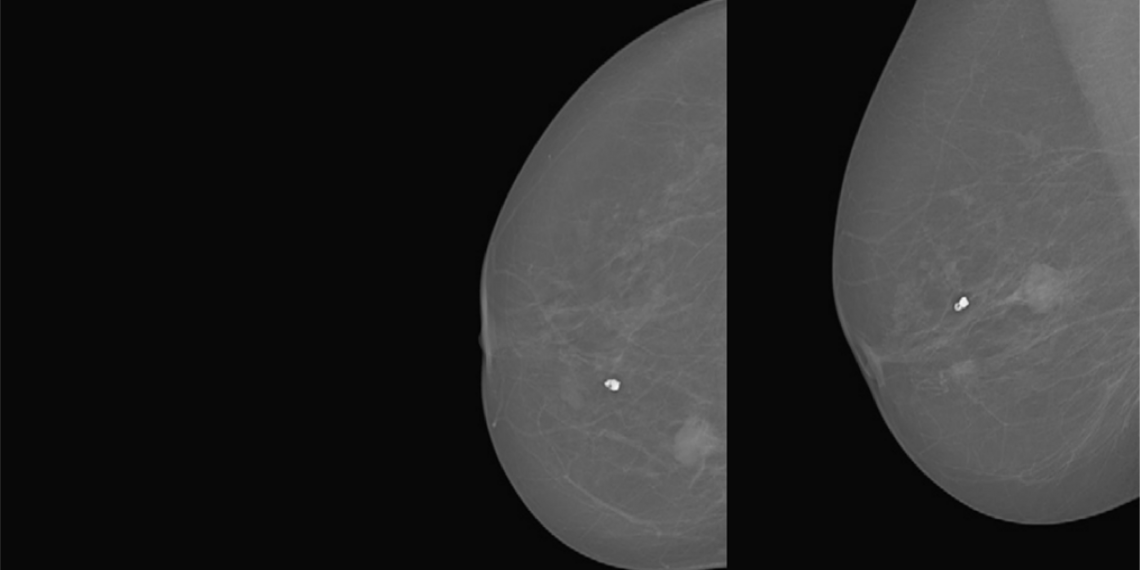

Researchers from INESC TEC’s Centre for Telecommunications and Multimedia (CTM) participated in the international study “Evaluation of Combined Artificial Intelligence and Radiologist Assessment to Interpret Screening Mammograms”, a reference research that proposes an A.I. system to support the radiologists’ decisions.

The main objective of the challenge and underlying study was to determine, in a thorough and unbiased manner, how current Machine Learning algorithms compare with the precision of human interpretation of mammography screening.

In this particular study, no Artificial Intelligence algorithm was able to overcome the accuracy of human interpretation. However, the study suggests that merging the results of several algorithms can actually improve the experts’ accuracy. In other words, combining the information obtained by the radiologists with the information obtained by algorithms, allows for diagnoses that are more accurate.